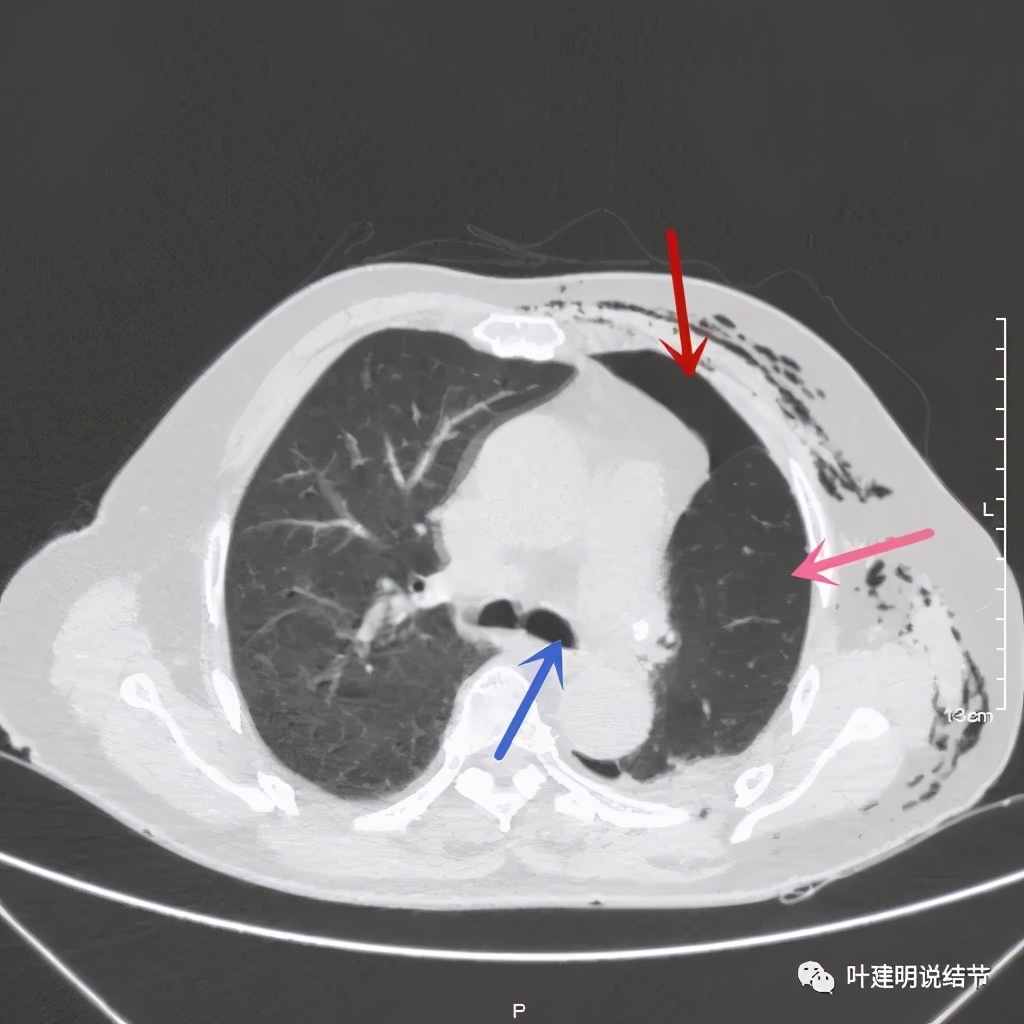

术后第二天患者乏力纳差,起不了床!而且CRP也大于100,我们的神经又紧张起来,怕支气管胸膜瘘,怕感染、怕有并发症发生。还好化验后是低钾,予以补充钾与镁2天后胃纳与精神均有明显改善,我们再加用静脉高营养支持治疗,补充白蛋白,情况逐渐好转。我们也于术后第4天查了CT,发现如下:

下叶膨胀良好,上叶残腔不大,蓝色箭头示左主支气管

下叶膨胀良好,上叶残腔不大。桔色箭头示吻合口处,通畅

以上图像示下叶膨胀良好,上叶残腔不大,紫色箭头示吻合口以远的支气管通畅,肺膨胀佳